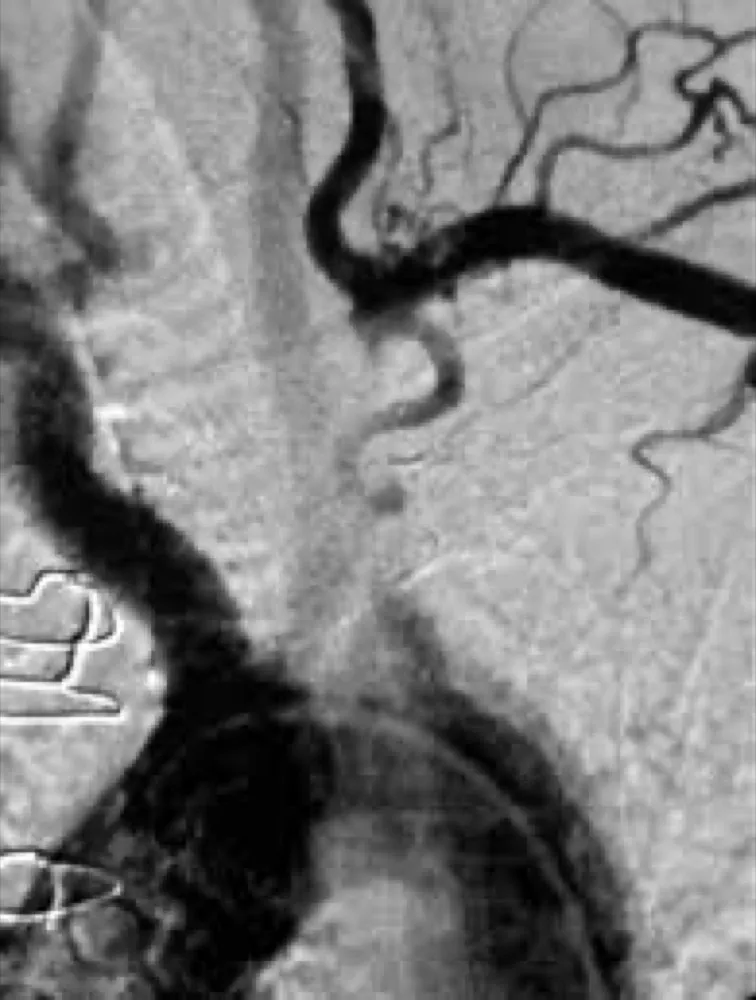

DRC indeterminada ou você esqueceu de fazer o básico? Veja tudo aqui

DRC “indeterminada” raramente é falta de diagnóstico — quase sempre é falta de método. Tempo de evolução, urina bem avaliada, USG renal e história clínica dirigida mudam conduta e evitam erros comuns na prática nefrológica.